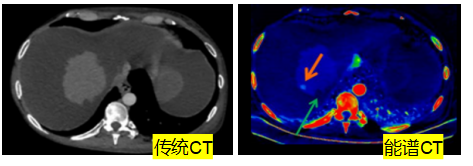

普通的影像检查看的是“形态”,而我们的能谱成像技术,能更进一步看清组织的“成分”,实现从“看得清”到“看得准”的飞跃。

1、肿瘤检查:抓住最佳治疗时机,避免无效治疗。

发现更早:识别常规CT难以发现的小结节、微转移灶。 评估更准:精准判断肿瘤治疗后是坏死、缩小还是仍在活跃,帮助医生及时调整方案。